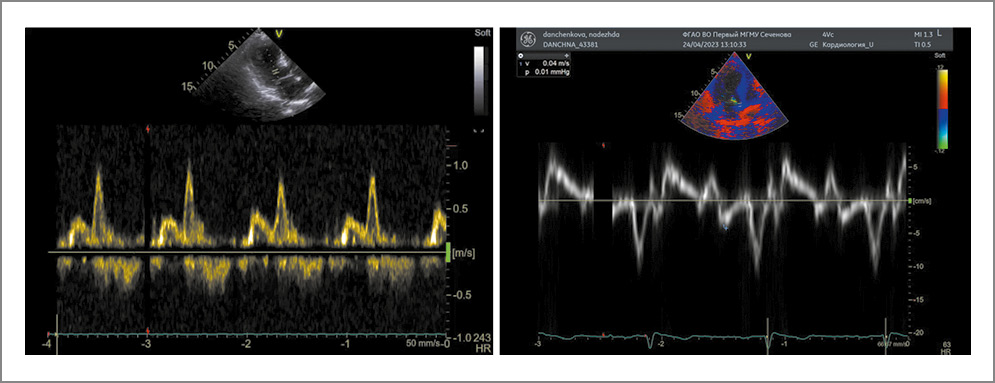

Принимая во внимание наличие специфических зон нарушения локальной сократимости, концентрическую гипертрофию ЛЖ с диффузным мелкозернистым свечением миокарда, интактные КА на фоне нормальных показателей тропонина I и высокого уровня NT-proBNP, определили векторы дальнейшего дообследования пациентки в рамках заболеваний СТ и ATTR-амилоидоз. С целью диагностики амилоидоза с помощью ЭхоКГ оценивали диастолическую функцию ЛЖ и показатель RASP (паттерн относительного сохранения систолической продольной деформации в апикальных сегментах). Выявили диастолическую дисфункцию 1-го типа (по типу нарушения релаксации) и показатель RASP 0,7, что не характерно для ультразвуковой картины амилоидоза (рис. 4).

Рис. 4. Диастолическая дисфункция ЛЖ по типу нарушения релаксации.